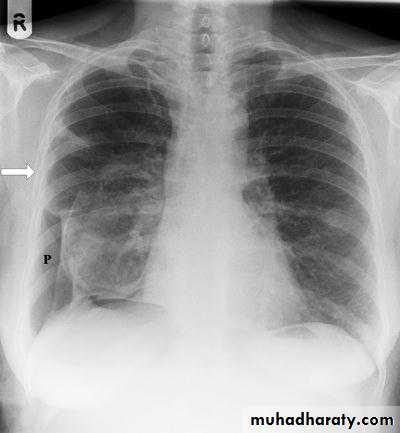

PNXDiseases of the Pleura Dr.Mustafa Nema. Baghdad College of Medicine 2013

Surgical emphysema may complicate PNX when air escape to subcutaneous tissuesDiseases of the Pleura Dr.Mustafa Nema. Baghdad College of Medicine 2013

PNX in

Diseased lungDiseases of the Pleura Dr.Mustafa Nema. Baghdad College of Medicine 2013